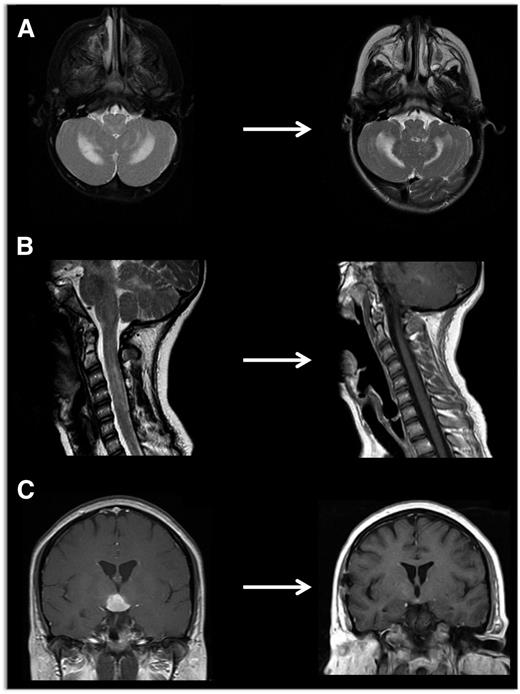

Neuroimaging of LCH lesions. These examples demonstrate typical manifestations of LCH CNS and spinal cord lesions. (A) Brain MRI demonstrates T2-hyperintensity in cerebellum classic for LCH neurodegenerative syndrome. In this case, the patient had radiologic and clinical response to treatment with cytarabine. (B) Spinal MRI demonstrates significant spinal cord lesions. This is a somewhat atypical case of a 13-year-old girl who had marginal response to cytarabine, then clofarabine. BRAF-V600E was detected in cells from the CSF, and the patient ultimately had radiologic and clinical response to vemurafenib. (C) Brain MRI demonstrates a pituitary mass classic for LCH, though differential diagnosis also includes germinoma, lymphoma, and pituitary hypophysitis. In this case, the lesion was biopsy proven to be LCH, and the patient responded to cytarabine therapy.

Neurodegenerative CNS LCH

Neurodegenerative CNS LCH is a syndrome of uncertain etiology characterized by relentless progression of central neurodegeneration that may occur even 10 years after presumed resolution of LCH lesions.53 Patients may develop clinical symptoms of dysarthria, ataxia, dysmetria, and behavior changes. MRI demonstrates hyperintensity of dentate nucleus and white matter of cerebellum on FLAIR and T2-weighted images, or hyperintense lesions of basal ganglia on T1-weighted images. There is also progressive atrophy of the cerebellum (Figure 6). These diagnostic radiologic findings may precede clinical symptoms by several years.46 A challenge in patients with only radiologic evidence of neurodegeneration is deciding when to treat. We perform regular neurologic exams with the Ataxia Rating Scale on patients with CNS-risk lesions and with LCH ND to document changes in tremor, kinetic functions, speech, and visual abilities.54 A score increased by 5 points indicating clinical deterioration and/or progressive changes on MRI merits consideration of systemic therapy. Similarly, we perform annual brain MRI on patients at risk to screen for development of LCH ND. Early intervention in patients with evolving symptoms is critical. IV γ-globulin and retinoic acid have been reported to stabilize progression of LCH ND.55,56 In an institutional series, vincristine/cytarabine was associated with improvement in clinical symptoms and MRI images in 6 of 8 patients.47 We therefore favor this strategy for patients with LCH ND. Some patients fail to respond to these therapies and have an inexorable decline in neurologic function over the course of years. As the etiology of ND LCH remains uncertain, it is not known whether MAPK inhibition could impact development or progression of ND LCH.